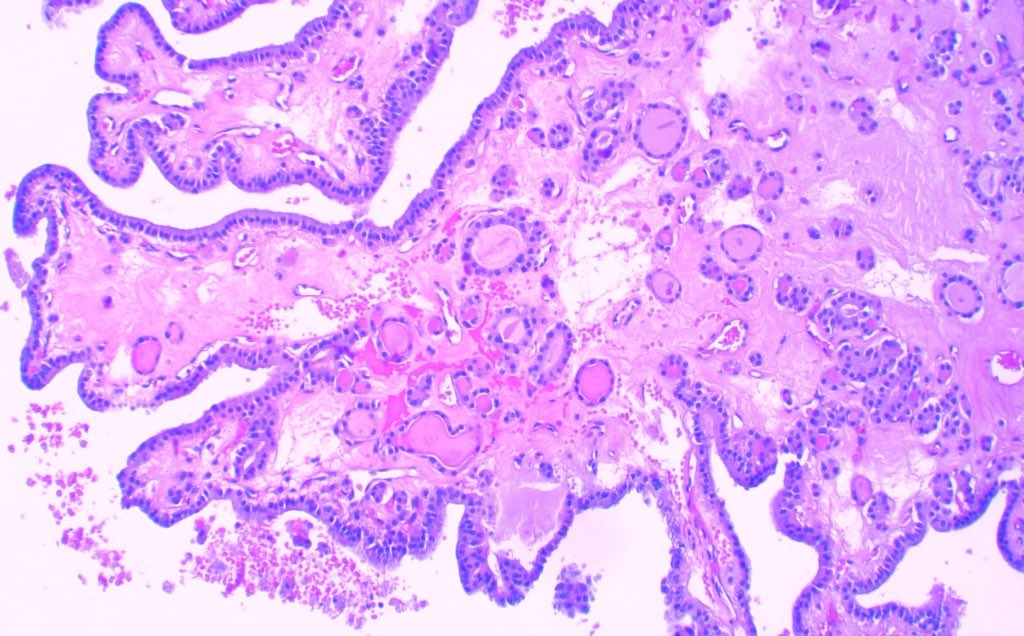

Papilla does not mean carcinoma in #thyroid #pathology Nodules with cystic degeneration can show beautiful ones 😁 Nuclear features are mandatory. #medicine #path #endocrine

JCandidoXavier's tweet image. Papilla does not mean carcinoma in #thyroid #pathology

Nodules with cystic degeneration can show beautiful ones 😁

Nuclear features are mandatory.